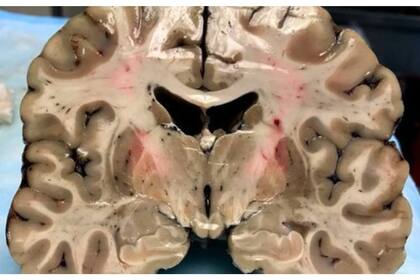

Al cortarlo en pedazos de 1,3 centímetros, los investigadores notaron la existencia de "cuevas" de un tamaño inusual en el centro del órgano, que se expandían a medida que el tejido cerebral disminuía. Según Caramelli, se trata de algo poco común para una persona de 27 años, edad en la que el cerebro suele ocupar casi todo el cráneo.

El equipo de McKee también observó que el septo pelúcido, una membrana que divide los dos lados del cerebro, estaba perforada, situación que suele ocurrir con los pacientes que padecen CTE.

No obstante, el principal indicio de esa enfermedad se encontró cuando colocaron el cerebro de Hernández debajo del microscopio y se percataron de una acumulación excesiva de proteína tau, que mata las células nerviosas.

Es por este proceso que las conexiones entre las áreas cerebrales que procesan determinadas funciones, como las emociones y memoria, dejan de funcionar normalmente. En el caso de Hernández, la proteína tau apareció por toda la corteza frontal, la parte del cerebro que controla la toma de decisiones, los impulsos y la inhibición.

También se había expandido a las amígdalas, que regulan emociones como el miedo o ansiedad, y otras partes del cerebro como el hipocampo, que se asocia principalmente con la memoria y con una parte del sistema límbico (responsable del comportamiento social).

El cerebro de Hernández se encontraba en un estado de la enfermedad de categoría tres, de una escala de uno a cuatro, que se suele encontrar en jugadores con un promedio de edad de 56 años. En rueda de prensa, McKee afirmó que el caso del exjugador de los New England Patriots se trataba de "uno que nunca hemos visto entre los 468 cerebros que hemos examinado".